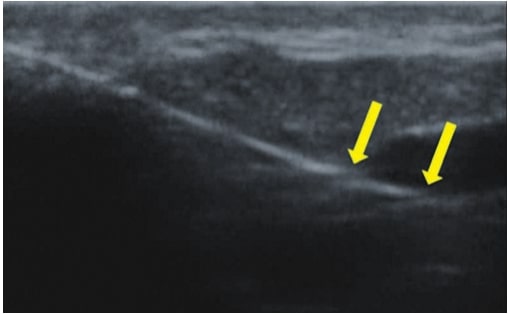

La sonographie Doppler permet l’imagerie des gros vaisseaux et des perforantes qui sont généralement situés dans les couches plus profondes du tissu sous-cutané (fig. 1). Malheureusement, la sonographie conventionnelle n’est pas capable d’imager les vaisseaux plus petits. Afin de visualiser les vaisseaux plus petits situés près de la surface de l’épiderme et dans la couche supérieure du tissu sous-cutané, l’EHF est utilisée (fig. 1). Grâce à l’utilisation de transducteurs dont les fréquences sont supérieures à 20 MHz, une image échographique à haute résolution est obtenue dans laquelle nous pouvons différencier des structures qui sont plus petites que 0,1 mm. Cependant, plus la résolution est élevée, moins la pénétration du faisceau ultrasonore dans les couches de la peau est profonde. Par conséquent, selon le transducteur et l’appareil, il est possible de pénétrer la peau jusqu’à une profondeur maximale de 20–30 mm. Une telle pénétration, associée à une haute résolution d’image, permet l’évaluation de vaisseaux sanguins même très petits (fig. 2). Pendant l’examen avec l’utilisation de transducteurs à haute fréquence, on peut évaluer avec précision le trajet et l’emplacement des petits vaisseaux dans la peau. Cela est particulièrement pertinent pour la sélection de la méthode de fermeture des vaisseaux et la planification de la procédure, car en pratique, la surface de la peau ne montre très souvent qu’un petit nombre de vaisseaux ou un léger fragment de vaisseau – ce n’est qu’après l’examen US que nous pouvons déterminer leur nombre réel et leur trajet. Pour une fermeture efficace du vaisseau, il est nécessaire de le faire sur toute sa longueur. Elle ne doit pas se limiter au fragment vu « à l’œil nu » à la surface de la peau, car la fermeture du fragment entraînera sa recanalisation rapide(7). Fréquemment, le vaisseau visible à la surface de la peau change de trajet, devient plus tortueux et se déplace vers les couches plus profondes de la peau(8). Par conséquent, le trajet de la veine et des perforantes doit être bien connu et déterminé avant la procédure. L’EHF permet également l’imagerie des perforantes entre les petits vaisseaux. De plus, outre l’évaluation du trajet et de l’anatomie, l’image échographique, grâce au logiciel d’échographie, permet également de déterminer les paramètres de base tels que le diamètre du vaisseau, l’épaisseur de sa paroi, la profondeur dans la peau ainsi que la présence ou l’absence de perfusion à l’intérieur du vaisseau(6) (fig. 3). Grâce au transducteur électronique multi-éléments d’une fréquence de 40 MHz introduit sur le marché par Ultrasonix, il est également possible de visualiser la perfusion des vaisseaux en mode Doppler couleur (fig. 4).

La sclérothérapie est une technique de fermeture des vaisseaux résultant de leur injection avec un sclérosant chimique. À l’heure actuelle, elle est couramment appliquée et se caractérise par, avant tout, de faibles coûts et le fait qu’elle est relativement facile à réaliser. La sclérothérapie est principalement indiquée pour la fermeture des veines réticulaires de plus de 3 mm, mais peut également être appliquée si les vaisseaux sont plus petits(10). Dans le cas de vaisseaux plus petits que 3 mm, il est plus difficile d’insérer une aiguille dans leur lumière, ce qui augmente le risque de complications(7). Dans une telle situation, l’EHF s’avère utile. Elle permet une visualisation précise du trajet du vaisseau et, par la suite, facilite l’exécution de la procédure sous guidage échographique (fig. 6). Ainsi, grâce à l’échographie, le risque d’administrer le sclérosant au-delà de la lumière du vaisseau, ce qui entraîne une nécrose, a été éliminé. L’imagerie par échographie à haute fréquence peut également être utilisée pour surveiller l’efficacité de la procédure.